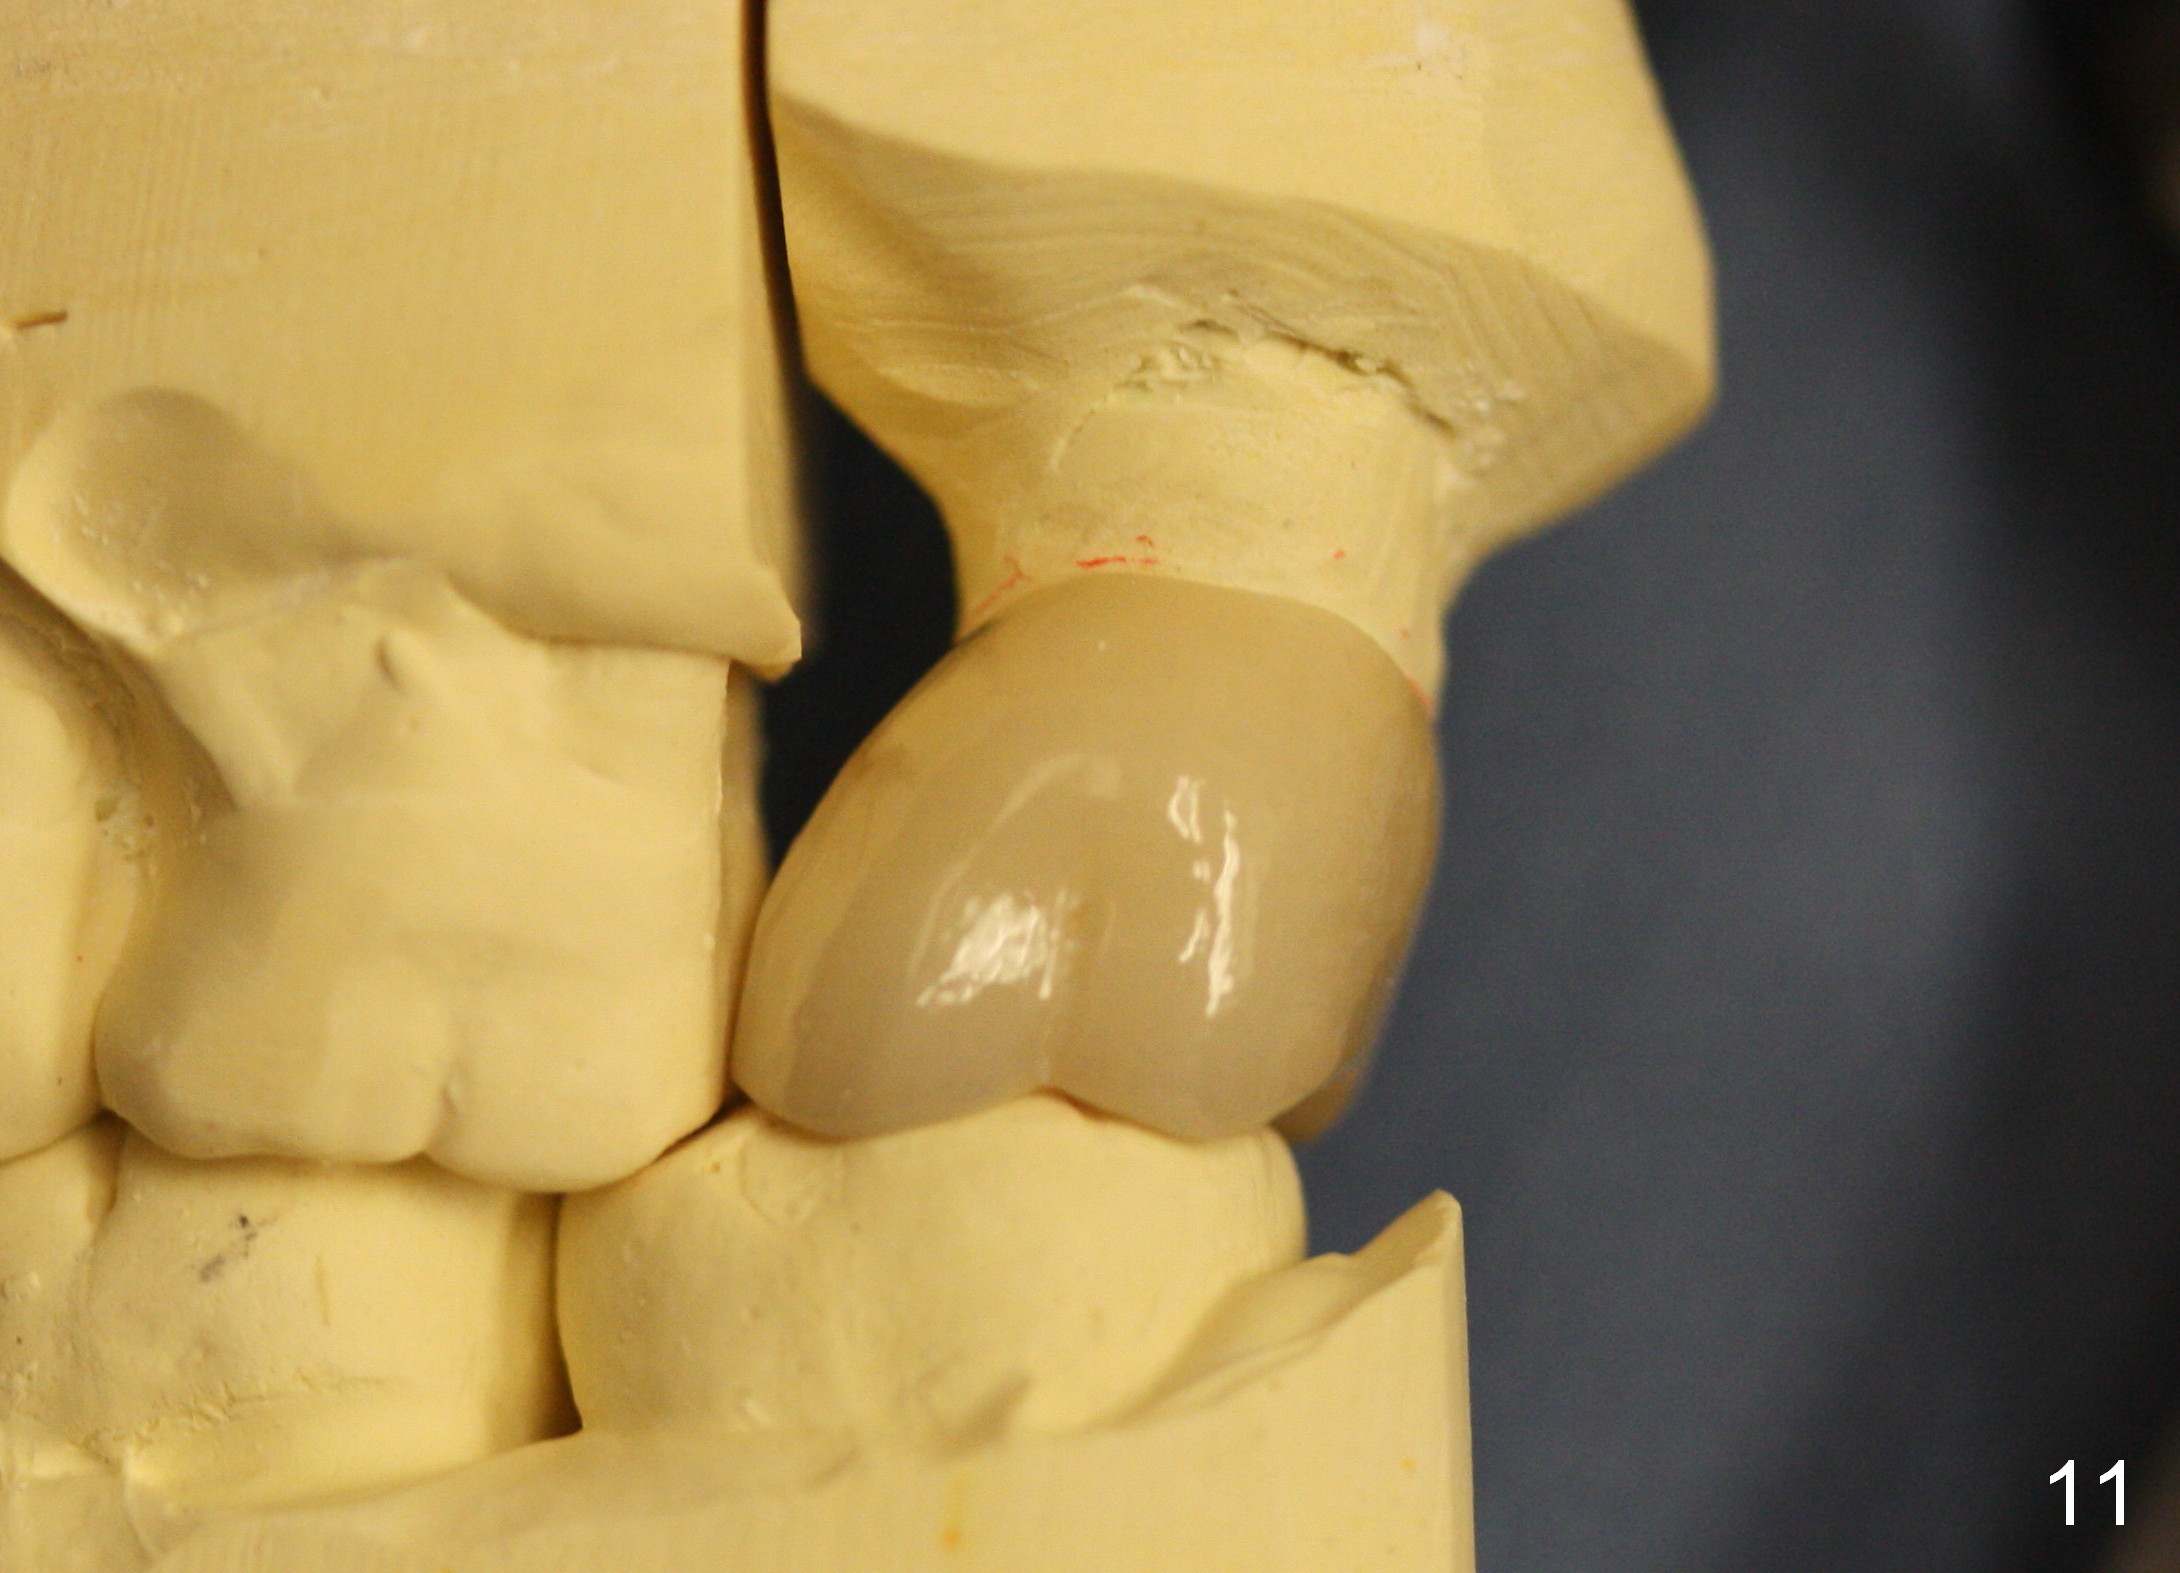

Model study shows that the implant is placed distally (Fig.9,11) in addition to buccal implant exposure (Fig.10 arrowheads). Postop, the patient complains of upper left discomfort, which is more likely associated with furcal infection of the tooth #14. The symptom disappears after use of water pik. Panoramic X-ray is taken 6 months post cementation (Fig.12).